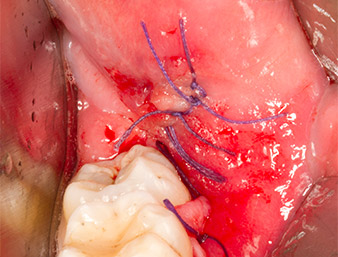

Subsequently, the autogenous bone tissue (Fig. 13) was placed into the alveole and the surrounding bone defect (Fig. 14). Collagen fleece covered the bone chips up to bone level as protection for the exposed nerve (Fig. 15). Sutures using vicryl thread, USP 4.0, were used to close the opened up soft tissue (Fig. 16). An Ibuprofen preparation (Seractil 400 mg, 3x1) and an antibiotic consisting of amoxicillin and clavulanic acid (Augmentin 1 g, 2x1) were prescribed postoperatively.